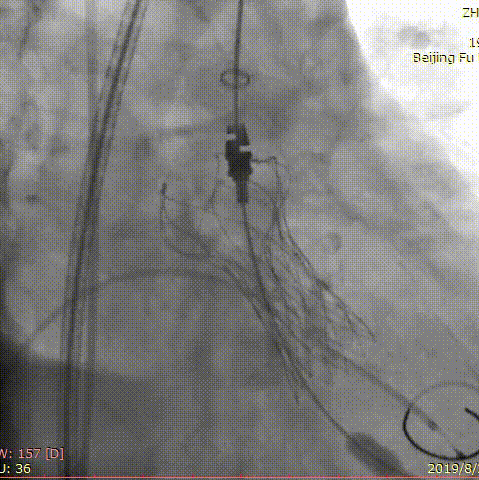

第二位患者是一名84岁男性,因发现心脏瓣膜异常12年,胸闷气短5年入院。曾于我院就诊,超声心动图提示主动脉瓣重度狭窄,2年前行经导管主动脉瓣球囊扩张术,术后患者仍有气短症状反复发作。此次入院后超声心动图提示主动脉瓣球囊扩张术后、主动脉瓣重度狭窄并少量反流,主动脉瓣平均跨瓣压差97mm,收缩期峰值流速6.3m/s,最大压差158.8mmHg。患者高龄、虚弱、消瘦(BMI仅18lg/m2),术前CT评估患者呈带嵴二叶瓣,L-R融合,主动脉瓣环21*29.6mm,周长80.6mm,面积494.7mm2,瓣上多平面测量结果如下。

右侧股动脉为主入路,应用20mm微创心通敖广球囊预扩张,植入24mm微创心通Vifaflow瓣膜,但术中造影提示瓣膜打开不理想,遂应用20*40mm球囊后扩张,术后造影提示无瓣周漏,超声提示主动脉瓣跨瓣压差仅2mmHg。

术前影像